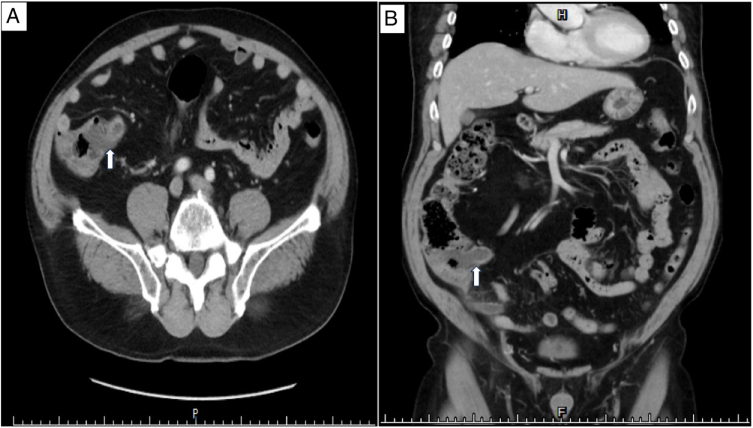

Introduction and clinical importance: Primary signet ring cell carcinoma (SRCC) of the appendix is an exceedingly rare malignancy with a non-specific clinical manifestations, and it often masquerades as acute appendicitis. Case presentation A 76-year-old man presented with acute abdominal pain and peritonitis. Abdominal computed tomography revealed relative acute appendicitis with peritonitis, and emergency laparoscopic partial cecectomy with appendectomy revealed gangrenous appendicitis with perforation. A histopathological examination revealed a primary appendiceal signet ring cell carcinoma (PASRCC).